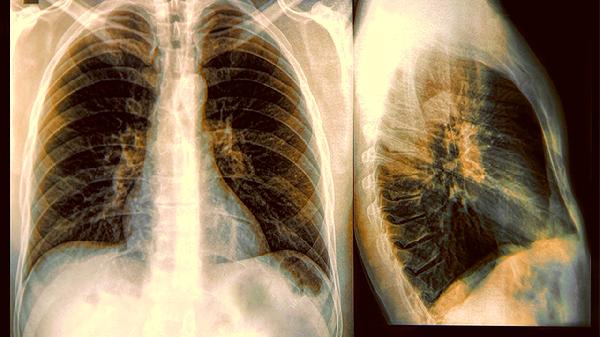

5、辅助肺结核恢复

肺结核恢复期出现低热、盗汗等阴虚症状时,养阴清肺丸可作为辅助用药。但需与抗结核药如异烟肼片联合使用,不能替代正规抗结核治疗。用药期间应监测肝功能,避免与伤肝药物同服。